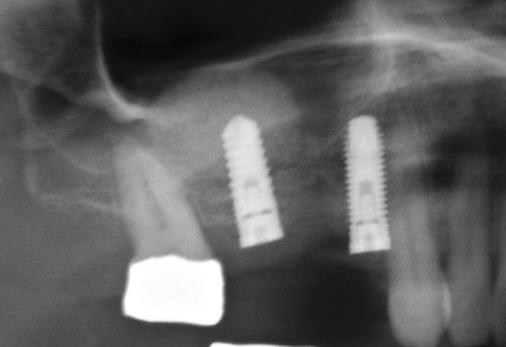

Tento výkon se nazývá sinus lift - aplikace kostního granulátu do čelistní dutiny

Od roku 1985 je tento problém řešen augmentační operací nazývanou sinus lift.

Jedná se o vyzvednutí membrány, která čelistní dutinu vystýlá, pod vyzvednutou membránou vznikne kapsa, kam se umístí augmentační materiál, do kterého se zavedou implantáty.

Vhojení implantátů se při této operaci prodlužuje na 6-12 měsíců.